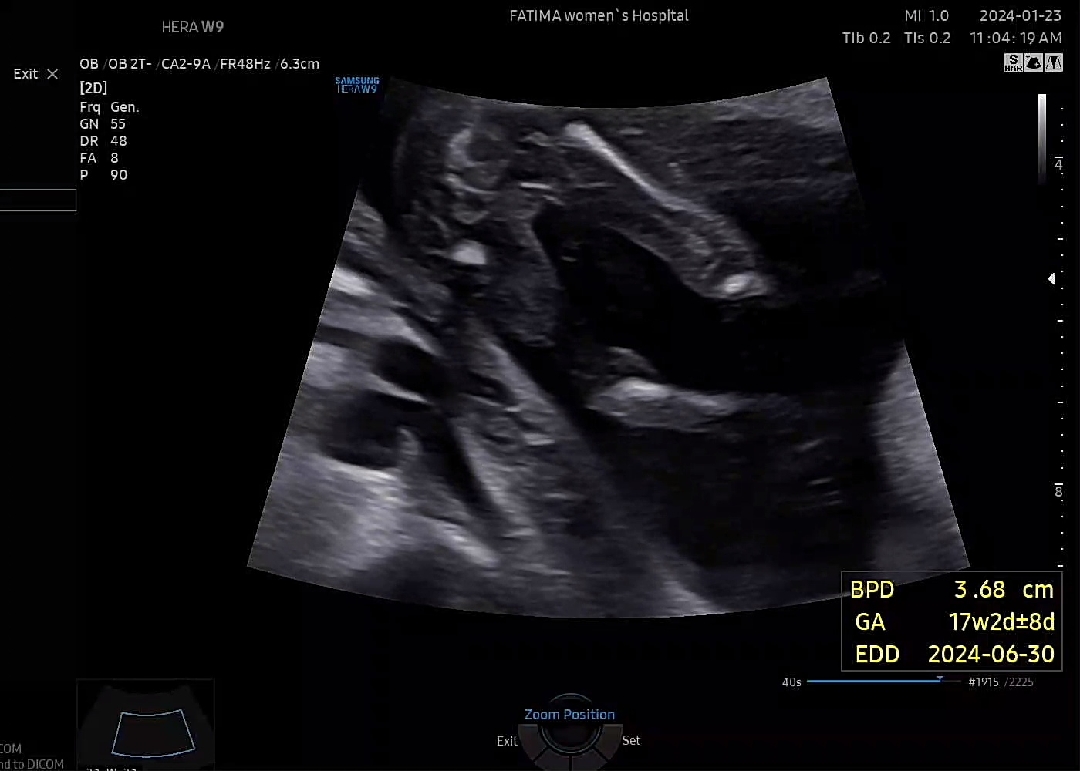

딸맘이래요~~

다리꼬우고 있어서 잘 안보이다가 의사쌤이 꼭보여주겠다고 ㅋㅋㅋ초음파만 한참했네요 17주차라 반전은 잘 없다더라구요 ! 잘자라고 있어 다행입니다 ^^